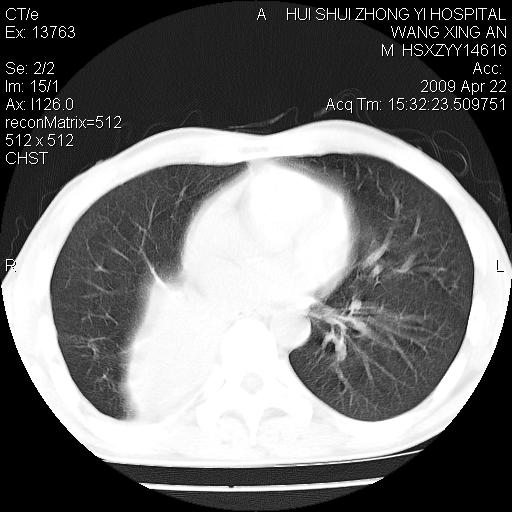

标题: CT19534:患者男、46岁咳嗽、胸痛半月。 [打印本页]

标题: CT19534:患者男、46岁咳嗽、胸痛半月。

1、右下肺中央型肺癌并右肺转移,右肺下叶不张。(肿块围绕右肺下叶支气管生长,致管腔闭塞右肺下叶不张;右肺有结节影)。

2、右侧胸腔积液。

3、右中上肺陈旧性肺结核(右肺见纤维化病灶及点状钙化)。